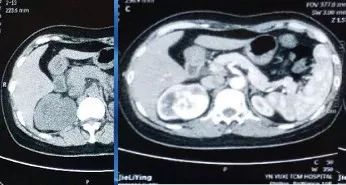

患者:女性,47歲,因血尿、右側(cè)腰腹部疼痛入院,CT、IVP等檢查。

診斷:右腎惡性腫瘤。

分析:腫瘤生長于右腎中下級、大小約5cm、腎盂破壞可能,未發(fā)現(xiàn)腎靜脈及下腔靜脈瘤栓、右腎上腺無浸潤;擬行保留同側(cè)腎上腺根治性腎切除術(shù)。